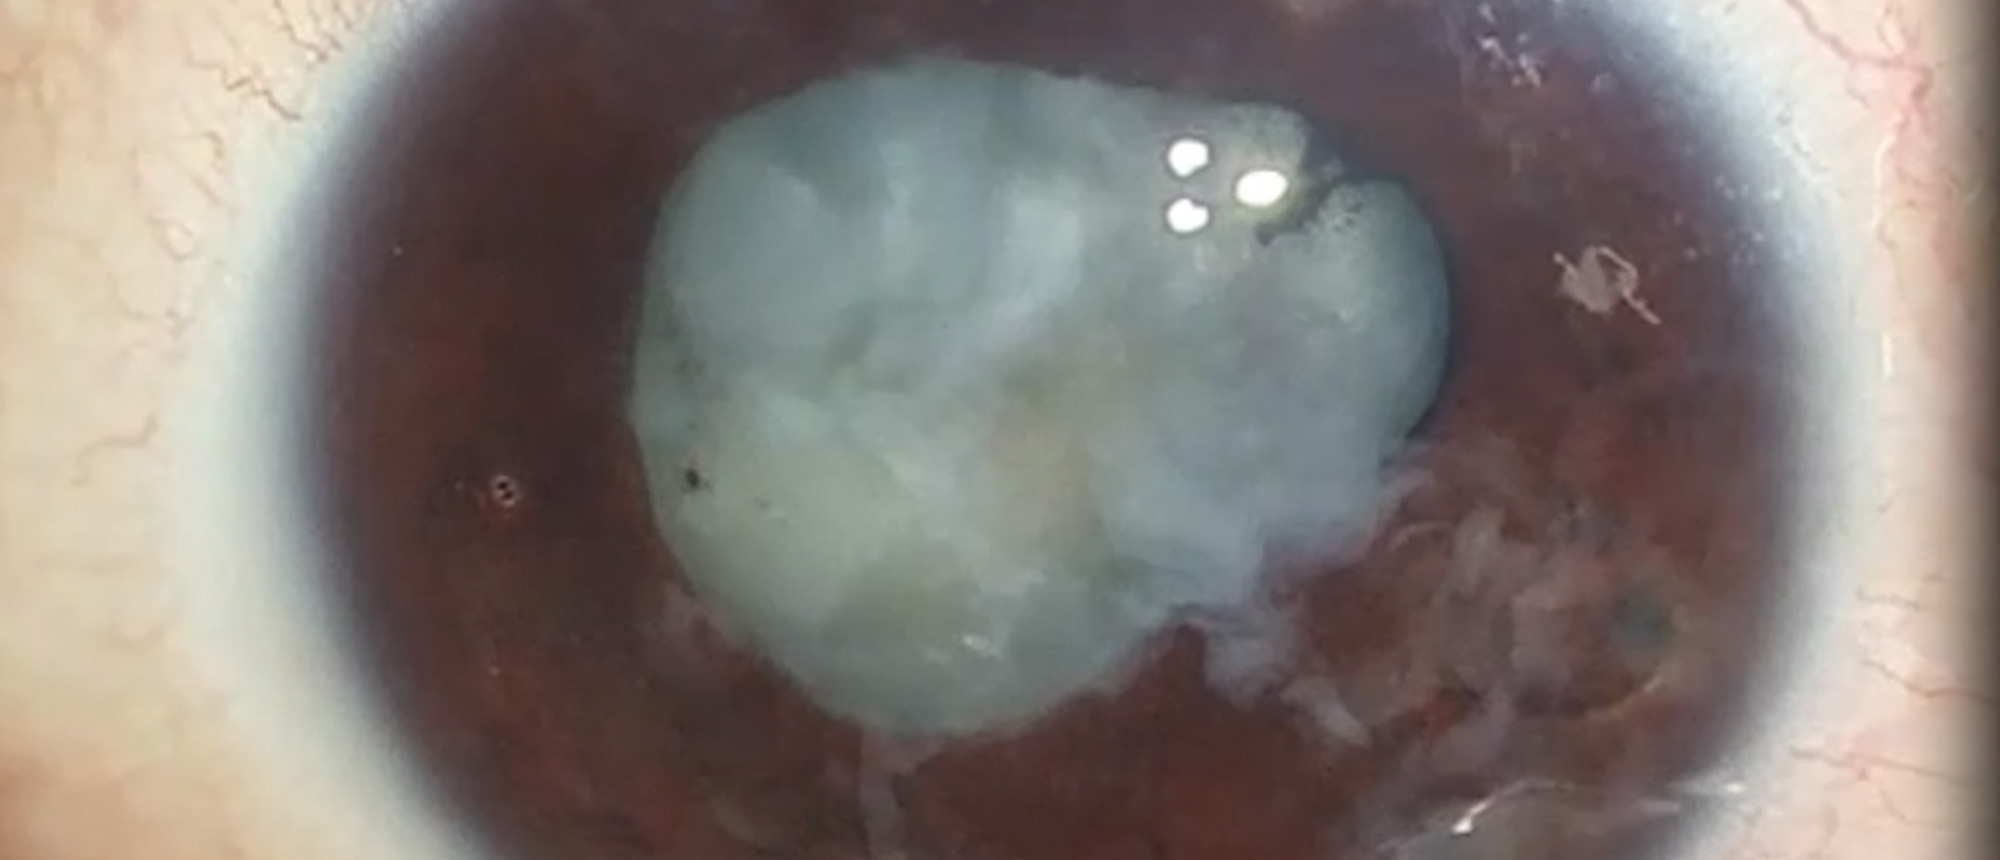

White Cataract with Pre-existing Posterior Capsule Rupture from Intravitreal Injection

Abstract A patient who underwent an intravitreal anti-vascular endothelial growth factor injection developed a white cataract after his procedure. Careful examination and ultrasonography revealed a white cataract with a posterior capsule violation, likely from the intravitreal injection. The patien…

White Cataract with Pre-existing Posterior Capsule Rupture from Intravitreal Injection A patient who underwent an intravitreal anti-vascular endothelial growth factor injection developed a white cataract after his procedure. Careful examination and ultrasonography revealed a white cataract with a p…